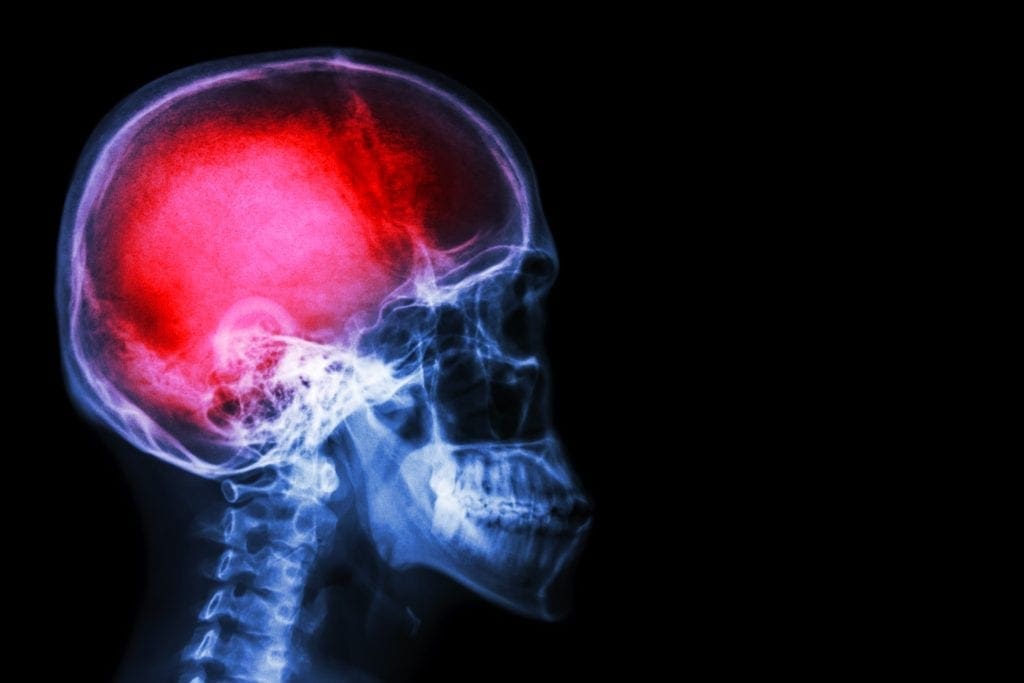

Perda dos movimentos na face, alteração na fala, na coordenação motora ou dor de cabeça súbita podem ser sintomas de um Acidente Vascular Cerebral (AVC). De acordo com o coordenador do Pronto-Socorro de Neurologia do Hospital 9 de Julho (H9J), Dr. Rafael Paternò, a doença é uma das principais causas de morte no Brasil. “Segundo a organização Mundial de AVC (World Stroke Organization) uma em cada seis pessoas podem ter AVC ao longo da vida. Porém, em 90% dos casos o problema pode ser evitado com hábitos mais saudáveis”.

A doença pode lesar partes do cérebro e apresenta-se de duas maneiras: obstrução de uma artéria que impede a passagem do sangue (AVC Isquêmico); ou quando um vaso na região do cérebro se rompe e causa hemorragia (AVC hemorrágico). De acordo com o Ministério da Saúde, mais de 100 mil brasileiros perdem a vida, ao ano, em decorrência de doenças cerebrovasculares.

A confirmação do tipo de AVC é realizada por meio de exames de imagens específicos, como a tomografia, ressonância ou angiografia dos vasos cerebrais. “O AVC acontece subitamente, e a partir daí cada minuto é importante para o resultado final. É imprescindível um serviço de emergência organizado e preparado para um atendimento ágil” conclui o Dr. Paternò.